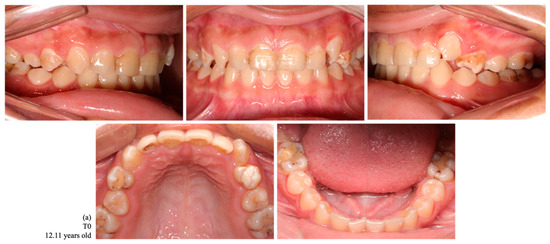

Figure 2.

Intraoral photographs of dental occlusion of a female indigenous participant, a habitant of the Assurini village, with no tooth loss at T0 (a) and with a loss of 10 permanent teeth at T1 (1.7, 1.6, 1.4, 1.1, 2.4, 2.5, 2.7, 3.7, 3.6, and 4.6) (b).